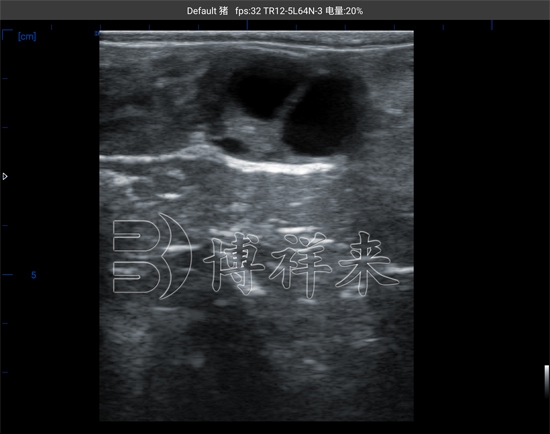

在母牛的发情周期中,卵巢内会经历一系列卵泡发育和退化的过程。一般情况下,一个完整的发情周期大约为21天,在周期内会出现多个卵泡波,但最终只有优势卵泡能够成熟并排卵。通过使用牛用B超机对母牛卵巢进行扫描,技术人员可以在屏幕上清晰看到卵泡的形态和大小变化。超声图像中,卵泡通常呈现为黑色圆形或椭圆形的无回声区域,边界清晰,通过测量其直径即可判断卵泡的发育阶段。通常情况下,当优势卵泡直径逐渐增大并接近成熟阶段时,就意味着排卵时间即将到来。

在实际生产中,牛用B超测卵泡的主要目的是判断卵泡是否已经达到排卵前的成熟状态。研究和实践经验表明,当母牛卵泡直径达到一定范围时,通常会在较短时间内发生排卵。通过连续几天的超声检测,技术人员可以观察卵泡的增长速度。如果检测发现卵泡直径持续增大,并且卵泡壁变薄、形态趋于圆润,这往往意味着卵泡已经接近排卵阶段。此时结合母牛的发情行为和其他生理指标,就可以更准确地确定人工输精的**时间,从而显著提高配种成功率。